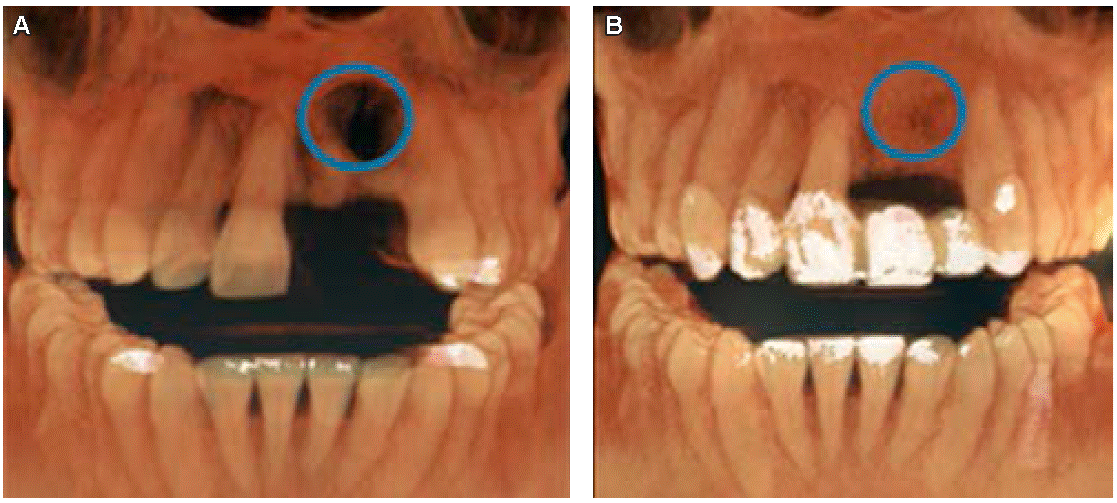

La paciente portaba una prótesis parcial removible en mal estado, que involucraba los órganos dentales 21 y 22 como se observa en la Figura 1. Además presentaba un defecto óseo de la cresta de tipo horizontal, clase 1 según la clasificación de Seibert: pérdida de tejido en dirección del vestibulopalatino (grosor) con altura adecuada como se muestra en las Figuras 2AyB.

De acuerdo con la nomenclatura de la Federación Dental Internacional (FDI), la paciente tenía caries oclusales en molares y premolares, caries de cíngulo, restauraciones con amalgama, fractura en distal y caries en cíngulo del OD 23 y cuatro dientes ausentes (Figuras 3AyB). De igual forma mostró cálculo dental y tejido gingival inflamado.